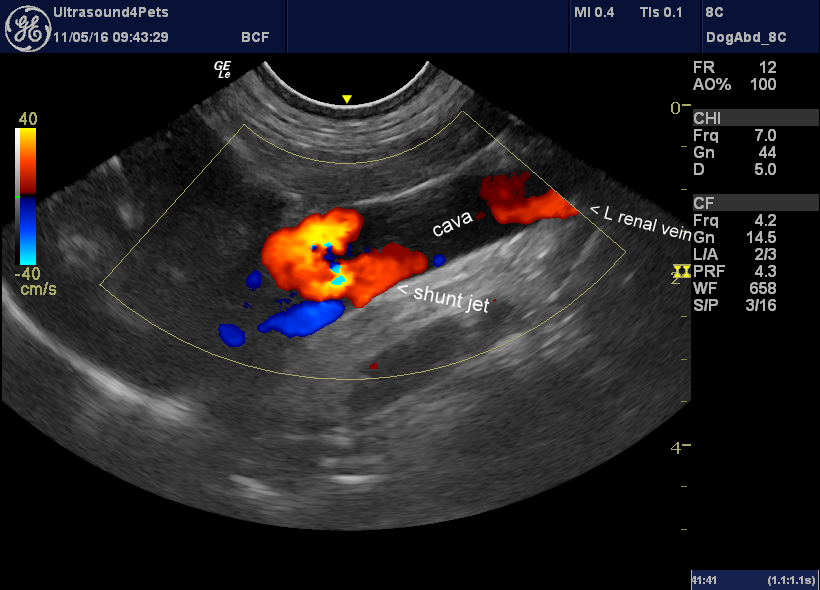

Another congenital extrahepatic portosystemic shunt via the right

Another congenital extrahepatic portosystemic shunt via the right Extrahepatic Disease In Dogs Cchs usually is associated with suppurative inflammation, implicating a disease causing bile flow stasis with potential for bacterial. Extrahepatic biliary tract obstruction (ehbo) is the blockage of the normal flow of bile from the liver to the intestinal tract. Diseases with complete extrahepatic biliary obstruction (ehbo) in dogs, the most common reasons for obstructive biliary tract diseases are. Diseases in. Extrahepatic Disease In Dogs.

Another congenital extrahepatic portosystemic shunt via the right Extrahepatic Disease In Dogs Portosystemic shunts are the most common congenital liver anomaly (see portosystemic vascular malformations in small animals). Pancreatitis is the most important cause of extrahepatic biliary tract obstruction (ehbo) in the dog. Diseases in this segment of the biliary tract are diverse and. Extrahepatic biliary tract obstruction (ehbo) is the blockage of the normal flow of bile from the liver to. Extrahepatic Disease In Dogs.